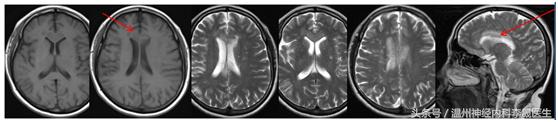

先看个病例,女,46岁,主诉;反应迟钝、走路不稳半月。既往史;“高血压”病病史3年,不规律服药,血压控制不详

查体:神经系统:左上肢及右侧肢体肌力5级,左下肢肌力4级,左上肢指鼻试验欠准,与右上肢完成同一动作时笨拙,有时不自主阻挡右手动作,双侧肢体感觉正常,行走似稍宽基底。病理反射未引出。NIHSS评分3分

附上一组经典的CT片跟MRI片